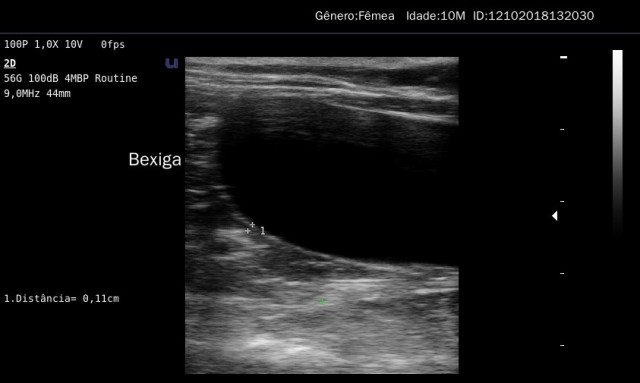

Ultrassonografia

O exame de ultrassonagrafia é uma ferramenta diagnóstica dinâmica e que permite visualizar o funcion...